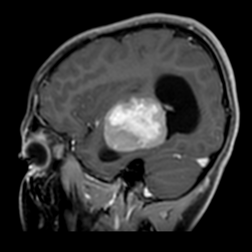

MRI outside hospital was done which was re-reported in our centre as Bilateral temporal lobe enhancing lesions. The left temporal lobe mass was larger in size and causing right-sided midline shift causing compression of the third ventricle with upstream hydrocephalus and transependymal seepage. These masses were reported as of neoplastic etiology, likely low-grade gliomas. Then MRI Brain with contrast was repeated which showed Bilateral intraventricular masses which are more or less stable in sizes causing hydrocephalus and compression effect at the level of the third ventricle towards the right side. Differentials included intraventricular tumors. No adjacent invasion is seen.

Figure 3: Lesion on T1 post contrast sagittal brain MRI.

The mean age of onset with nodal disease is 20.6 years with a male to female ratio of 1.4:1 [6,17]. Patients who develop intracranial involvement, however, become symptomatic at a mean age of 34.9 years, with a strong male preponderance. In intracranial RDD, the most involved structures are the suprasellar region, cerebral convexity, parasagittal region, cavernous sinus, and petroclival region [18,19]. Radiologically, the typical MRI findings include isointense to hypointense T1-weighted signals and hyperintense T2-weighted signals with homogeneous enhancement post-contrast. Bitemporal lesions often exhibit a dural-based, meningioma-like appearance [20]. Intracranial RDD is commonly confused with meningioma and requires tumor histopathology and immunohistochemistry for its definitive diagnosis.

Bilateral temporal lobe involvement with mass effect, brainstem compression and obstruction of the ventricular system at the level of the third ventricle causing hydrocephalus is exceptional. Differential diagnosis includes several diseases (such as bilaterla glioma, PNET) in this case. A precise diagnosis could not be reached on clinical grounds alone.